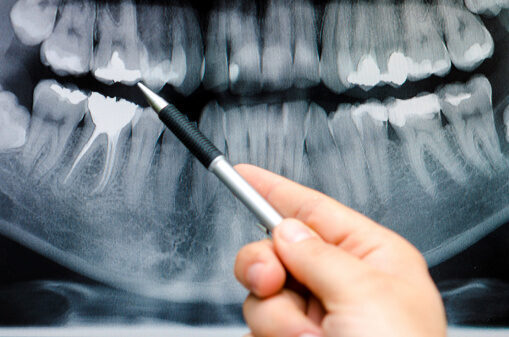

Niebezpieczne zmiany lub stany chorobowe w jamie ustnej nie zawsze są widoczne gołym okiem. Prawdę mówiąc, większość z nich kryje się i rozwija w takich miejscach jak obręb korzeni zębowych, tkanki okołowierzchołkowe, a nawet w kości. W takich właśnie sytuacjach niezbędne okazują się badania obrazowe, które pozwalają dokładnie określić rodzaj i stopień zaawansowania zmian, a dzięki temu wprowadzić odpowiedni plan leczenia. Nie tylko stomatologia zachowawcza czerpie korzyści z diagnostyki obrazowej. W równym stopniu stosowana jest ona także w leczeniu protetycznym, implantologicznym, a także ortodontycznym.

Nowoczesna diagnostyka obrazowa gwarantuje sporo korzyści zarówno dla lekarza, jak i pacjenta. Znacząco wpływa na usprawnienie procesu postawienia diagnozy, ułatwia komunikację z pacjentem, skraca czas wizyty. Dzięki szybkiemu przeniesieniu obrazu RTG na ekran monitora komputerowego zdjęcie wyświetlane jest natychmiast, a poprzez obróbkę cyfrową daje możliwość pozyskania dodatkowych informacji diagnostycznych. To wszystko zwiększa komfort pracy lekarza, a także poczucie bezpieczeństwa pacjenta. Równie ważną zaletą diagnostyki obrazowej jest możliwość przygotowania precyzyjnego kosztorysu i planu leczenia.

Diagnostykę obrazową dzielimy na wewnątrzustną i zewnątrzustną. W zakres zdjęć wewnątrzustnych wchodzą niewielkie obszary jamy ustnej, a także zdjęcia zgryzowe. Natomiast w zdjęciach radiologicznych zewnątrzustnych można wyróżnić m.in. badanie 3D, tomografię komputerową CT czy zdjęcie panoramiczne. Nowoczesne urządzenia do obrazowej diagnostyki radiologicznej to aparatura cyfrowa, która wyróżnia się minimalną dawką promieniowania, co skutkuje maksymalnym bezpieczeństwem pacjenta.